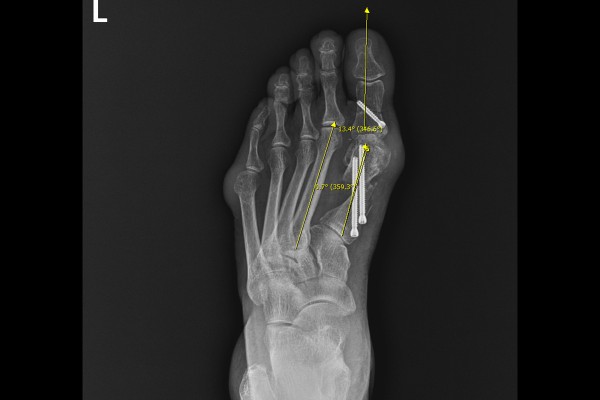

환자분의 발 상태를 정확하게 파악하기 위해 촬영한 X-RAY에서 엄지발가락이 휘어진 정도인 무지외반각은 49.2도(정상범위: 15도 이내),엄지발가락과 검지발가락 사이를 확인하는 중족골간각은 14.9도(정상범위: 9도 이내)로 좌측 발 무지외반증(Hallux valgus)을 진단하였습니다.

수술 후 무지외반각과 중족골간각 모두 정상범위내로 교정된 것이 확인됩니다.

수술 전/후 X-RAY를 비교했을 때 엄지발가락이 일자로 잘 교정된 것이 확인됩니다.